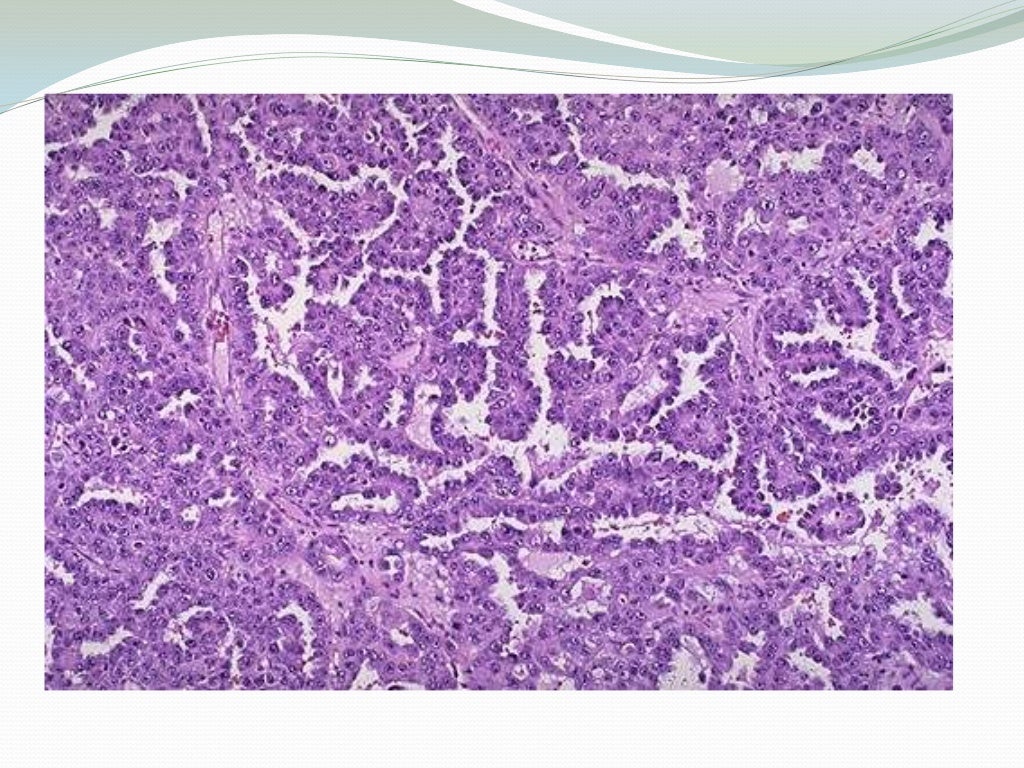

V Congreso Virtual Hispanoamericano de Anatomía Patológica CARCINOMA

Source: www.uninet.edu